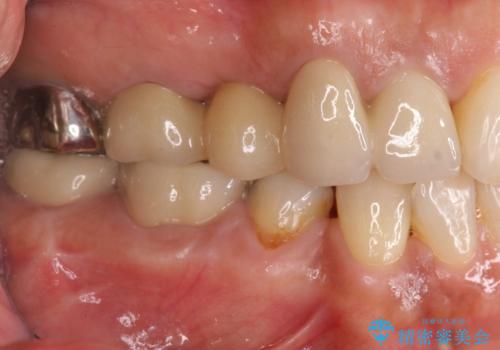

歯槽堤保存を併用し清掃性を高めたブリッジ治療

ブリッジによる補綴を行うことで周囲の歯の噛み合わせも改善ししっかりと噛むことができるようになりました。